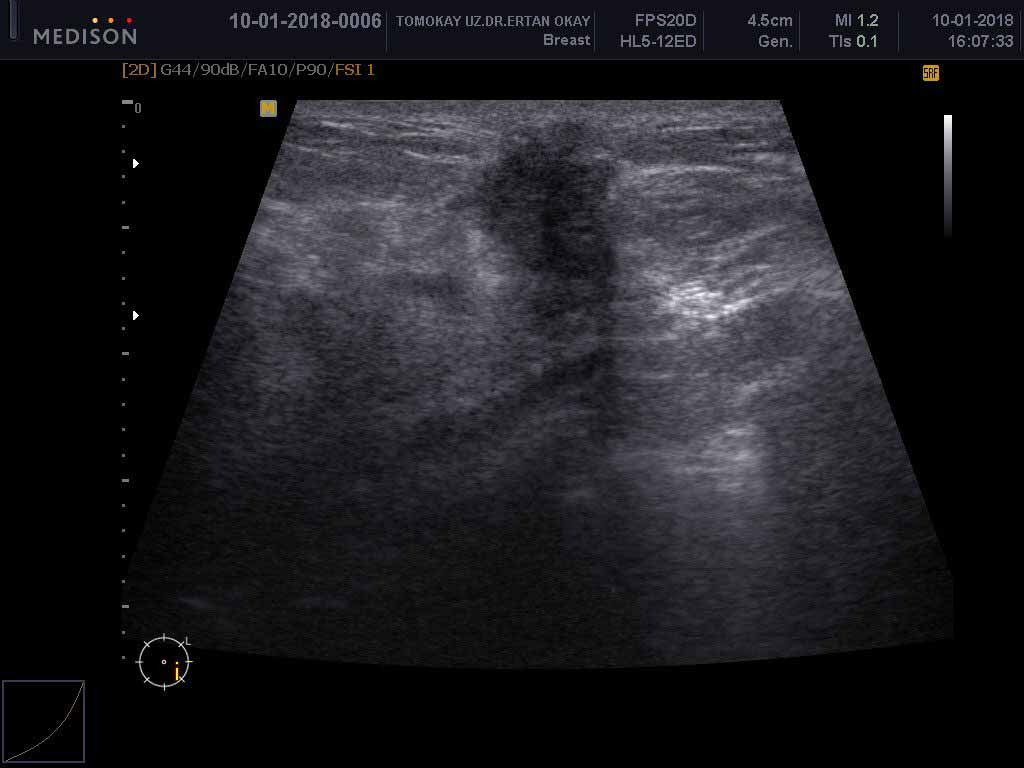

الموجات فوق الصوتية للثدي